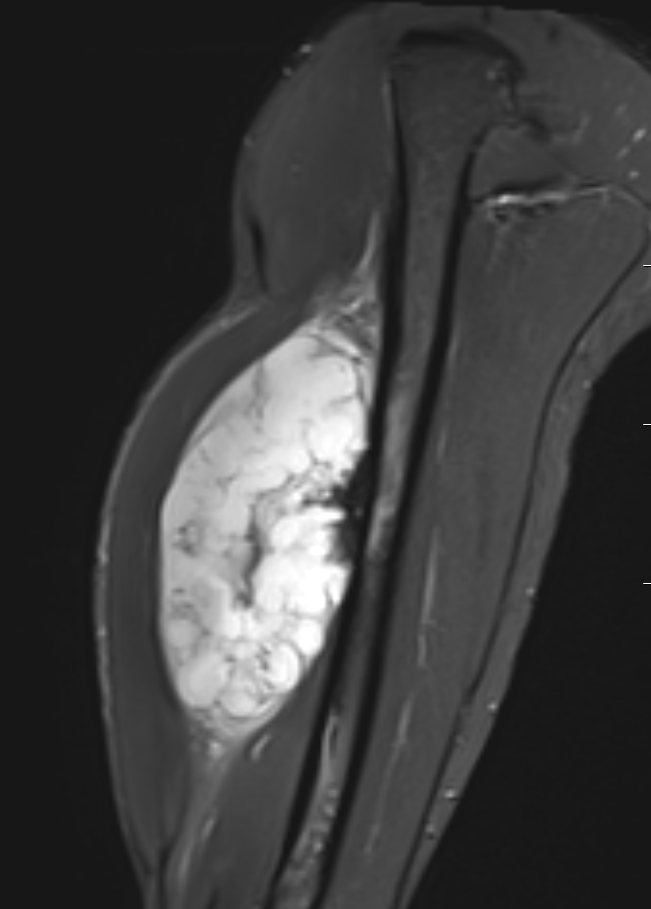

MRI

- MRI of 179 chondrosaroma

- features of high grade chondrosarcoma

- bone expansion, active periostitis, soft tissue mass and increased tumour length